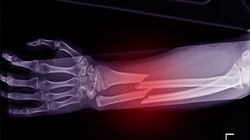

Choruje na Histiocytoze - postać tkanek miękkich (węzły chłonne). Obecnie czekam na wynik trepanobiopsji szpiku (szpik pobrany z biodra). Od kilku dni mam bardzo silny ból kości przedramienia lewej ręki (ból w nocy, takie rozpieranie od środka), boli mnie trzon kości (na środku). Ból jest tak silny, że nie mogę spać. Czy badanie rtg może wykazać zmiany? Jeśli tak to jakie badanie zrobić (rodzaj zdjęcia). Chciałabym na najbliższą wizytę do mojego lekarza, pójść już z rtg i badanie chcę zrobić prywatnie (chodzi mi o zaoszczedzenie czasu). Czy może nie ma sensu, bo jeśli jest też postać kostna to w trepanobiopsji szpiku to wyjdzie?

Tak, można je wykonać przed wizytą i pójść do ortopedy/lek. prowadzącego już z wynikiem.